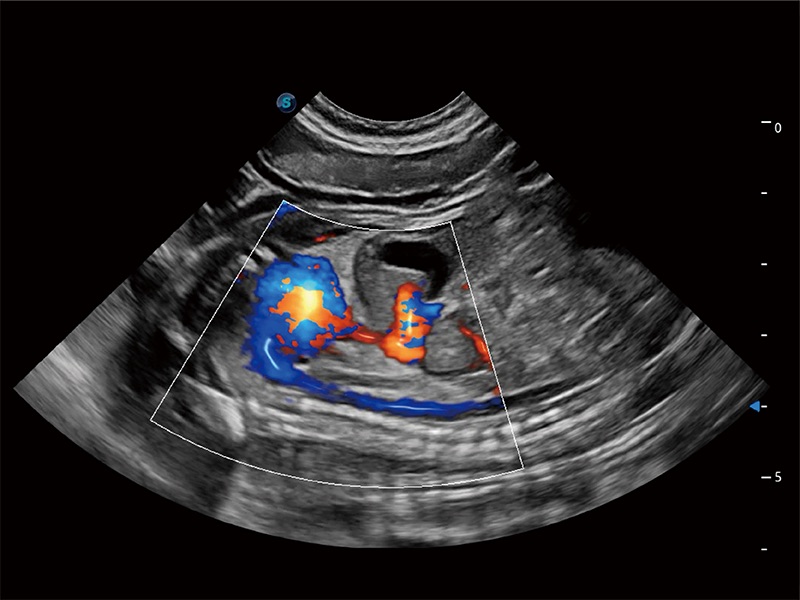

極大提升超低速微細(xì)血流的檢出能力,同時(shí)更精準(zhǔn)地濾除軟組織和超聲信號(hào),為獸用醫(yī)生提供以往無法通過常規(guī)血流獲得的疾病診斷信息。

在傳統(tǒng)二維血流成像的基礎(chǔ)上,呈現(xiàn)血流的立體感,具有動(dòng)感的生命力之美。即便是微小的血管也能輕松應(yīng)對(duì),提高了血流的視覺敏感性。